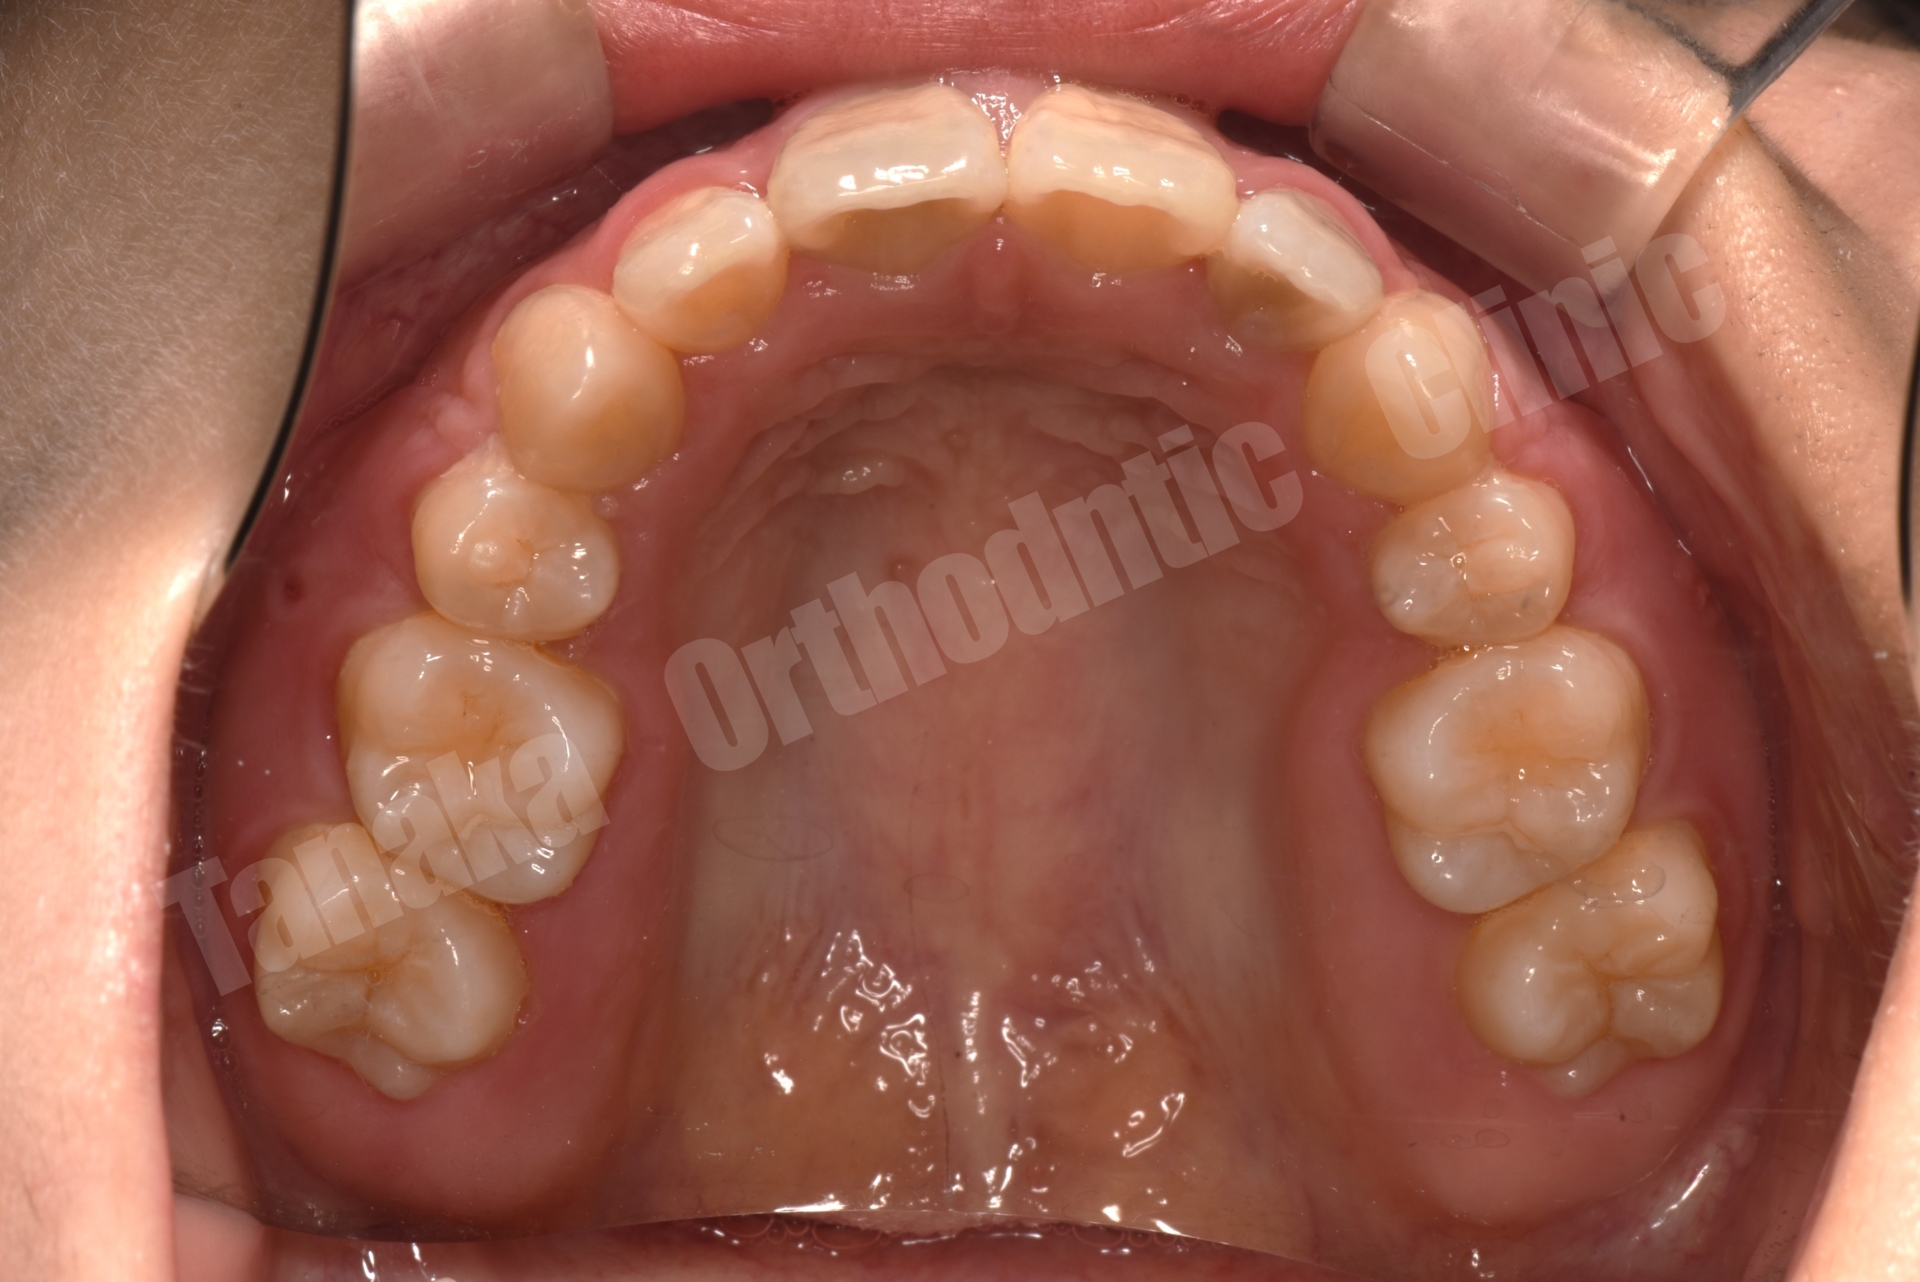

| 診断 | 上顎前突傾向(下顎骨の後方位)、上下顎歯列の叢生、上下左右8番を認める |

上下前歯部に叢生(がたがた歯列)

上顎には**最大限のアンカレッジ(MAX anchorage)が必要でした。

そのため、治療開示時に矯正用アンカースクリューを上顎に埋入する計画を立てました。

上下4本の小臼歯を抜歯後、矯正装置を装着

最終的には、整った歯並び・自然な口元・清掃性の改善を実現